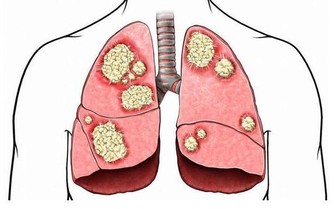

但如果莫名其妙出現尿頻尿急,夜尿增多,很可能是膀胱出現了惡性腫瘤或者是膀胱結石,導致膀胱儲存尿液的能力降低,伴隨著排尿頻繁的表現。